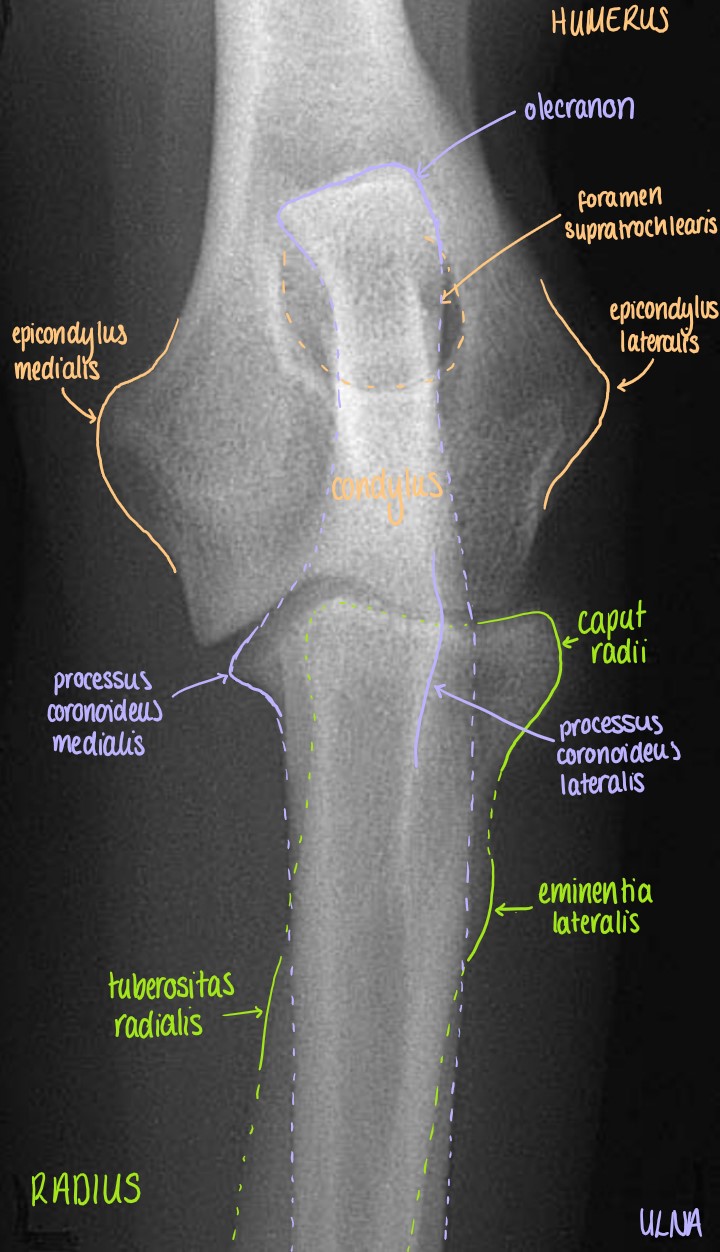

Articulatio Cubiti